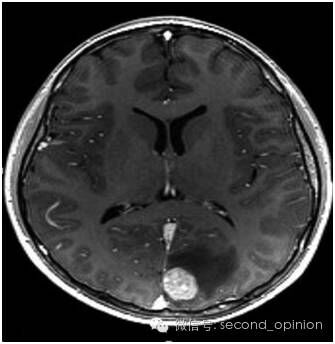

患者男性,65岁。2014年10月,患者感到腹部不适、头疼。检查和诊断结果为(1)高分化肝细胞癌,大小约10cm,肝硬化明显。(2)脑转移瘤,左枕叶处有大小约3cm的肿块。(3)II型糖尿病,需要胰岛素治疗。(4)慢性肾病;(5)中度高血压,有心衰病史。

患者处于肝癌晚期,肝癌病灶巨大且有脑转移,国内医疗机构不能实施外科手术治疗。经全球肿瘤医生网请意大利humanitas医院专家组远程咨询,患者于2014年11月10日赴意大利进行EDGE速锋刀无创手术治疗。先后对肝脏肿瘤和脑转移瘤进行EDGE治疗,在医院共治疗8天。每个肿瘤每天治疗1次,每次治疗时间约10分钟左右,肝脏肿瘤共治疗6次,脑肿瘤治疗4次。患者手术过程中无任何不适,每次治疗后正常回公寓休息。半年后,患者身体状态良好,体重明显增加。影像检查报告显示肝脏的巨大肿瘤被彻底清除,脑部肿瘤几乎完全消除,且没有复发。生化检查结果表明肝功能未见异常。

脑转移瘤治疗前3cm

脑转移瘤治疗后基本消失